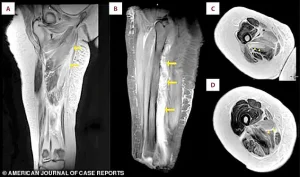

An MRI scan of the patient’s right thigh revealed widespread muscle swelling. The images, marked with arrows, pinpointed this fluid buildup in the inner thigh muscles (the adductor group) and, in a different view, showed similar swelling affecting the muscles at the back of the thigh

An MRI scan of the patient’s right thigh revealed widespread muscle swelling.

The images, marked with arrows, pinpointed this fluid buildup in the inner thigh muscles (the adductor group) and, in a different view, showed similar swelling affecting the muscles at the back of the thigh.